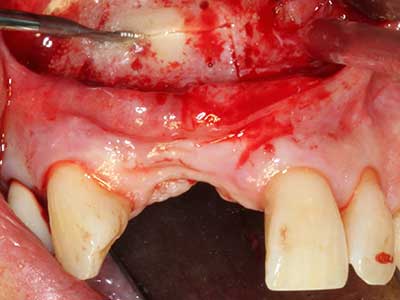

Quando le procedure chirurgiche vengono eseguite sull'osso nelle immediate vicinanze di strutture sensibili, come vasi sanguigni o nervi, gli strumenti rotanti pongono un rischio significativo di lesione iatrogena. I dispositivi piezoelettrici possono essere utili per la preparazione delle coperture ossee e la rimozione del tessuto duro in prossimità dei nervi, in particolare per la loro esposizione dopo una lesione iatrogena, ma anche durante la lateralizzazione dei nervi per le procedure di resezione e ricostruzione o il posizionamento di impianti (figg. 17-20). Il contatto leggero tra puntina piezoelettrica e nervo non causa generalmente danni, ma se si procede senza prestare attenzione con movimenti a sega o raccordi con residui di substrati ossei possono verificarsi danni al nervo temporanei o anche permanenti. Il rischio di danno, tuttavia, è considerato sostanzialmente inferiore al rischio presente utilizzando seghe o frese (Pereira, Gealh et al. 2014).

Fig. 18: preparazione di una copertura corticale con sega piezoelettrica per osso (Piezomed, W&H).

Fig. 19: sito chirurgico dopo neurolisi e rimozione dell'osteoma.

Fig. 20: la copertura ossea rimossa viene riadattata e fissata con una vite per osteosintesi (KLS Martin, Tuttlingen).